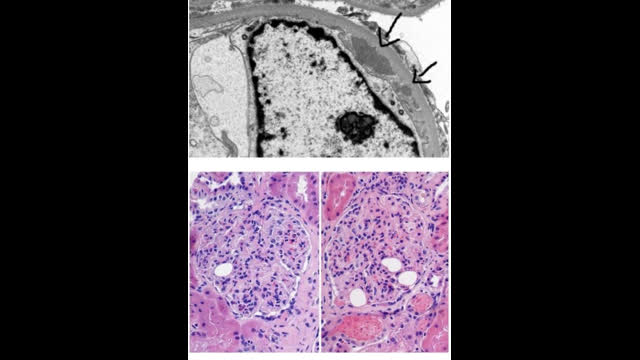

77-year-old man with a type 2 DM presents with worsening renal function and proteinuria